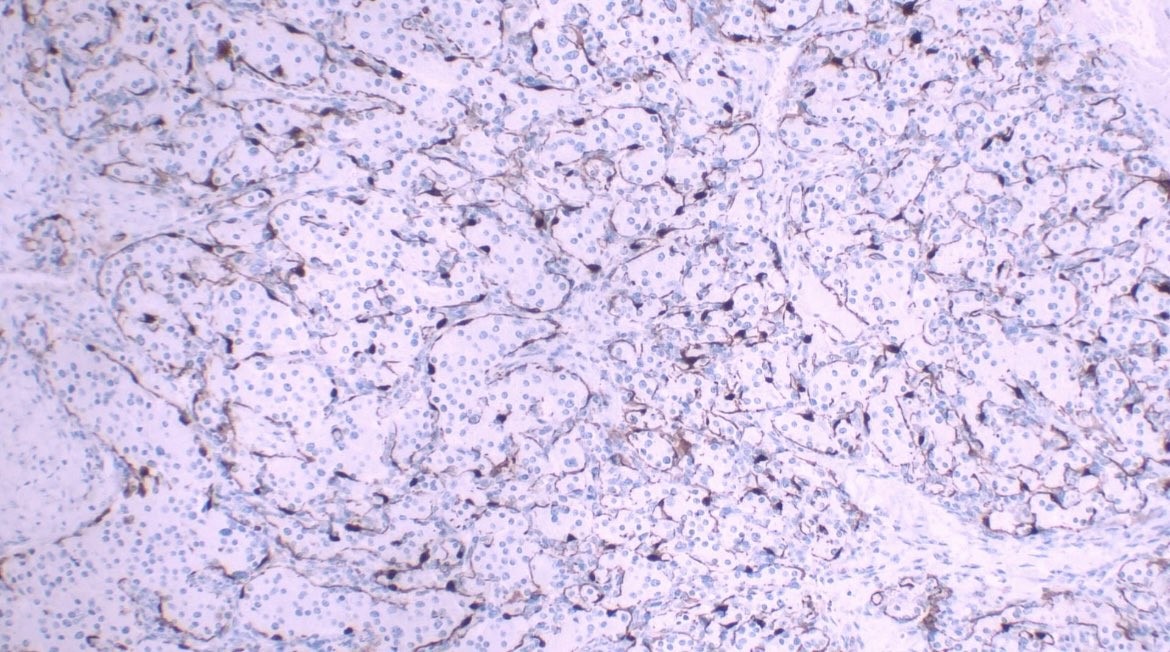

This was a curbside consult from #dermpath. Patient has a history of mastectomy for breast cancer and is now presenting with a chest wall skin nodule. What is your diagnosis? - IHC: p63 @wusm_pathology WashU Medicine Pathology & Immunology Education #breastpath #PathTwitter #PathX